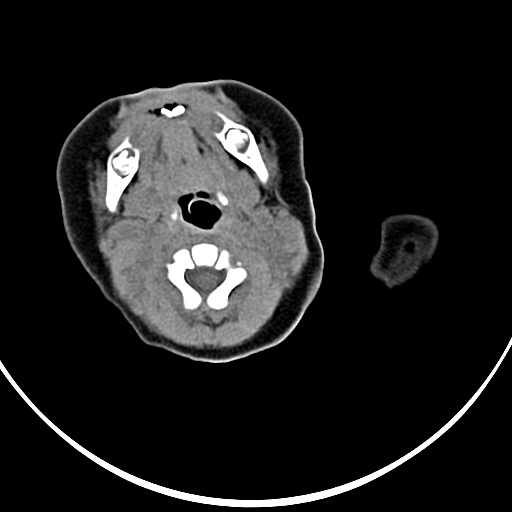

患者,男,1月,出生后一月,无明显诱因出现颈部左前方肿块。体检:左侧颈部轻度凸起包块,触之较硬。

患者,男,1月,左经部轻度凸起包块,质硬。